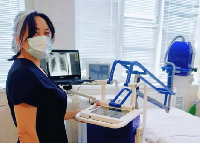

Выезд травматолога-ортопеда, рентгенолога Александра Валерьевича Дидковского.

На рабочем месте производится обучение работе на Вашем оборудовании.

Любого доктора можно быстро подготовить как рентгенлаборанта и дать необходимые знания для оценки рентгенограмм.

Мобильный рентгенаппарат + оцифровщик. Получение рентгеновского изображения на экране ноутбука. Вариант за 1,4 миллиона рублей под ключ.